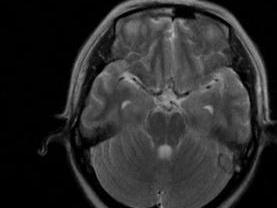

空泡蝶鞍   空蝶鞍综合征系指蛛网膜下腔伸展至蝶鞍内,使垂体缩小、压扁,蝶鞍扩大,可引起一定的临床症状。可为原发性,也可继发于垂体瘤手术或放疗后。

临床上以中年女性多见,可有头痛、视力障碍、视野缺损等表现。视野障碍主要累及鼻侧或双鼻侧,不规则多变。部分病人可有内分泌症状如闭经泌乳或单纯泌乳,垂体前叶功能减退等。